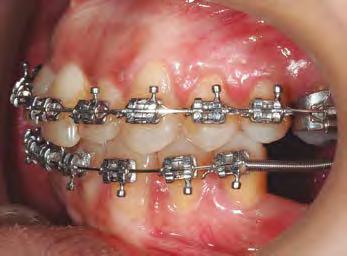

–Corticotomías y Ortodoncia. Ampliando límites del movimiento dental, por la Dra. Aranzazu Senosiain y cols. [50]

–Tratamiento de un caso de Ortodoncia y Cirugía Ortognática con placas preformadas y tecnología 3D, por la Dra. Elena Bonilla Morente y cols. [62]

–Uso del anclaje esqueletal como alternativa eficiente en el manejo ortopédico de clases III por deficiencia de maxilar superior, por el Dr. Carlos Becerra y cols. [74]

–MARPE, una alternativa a la disyunción en el paciente adulto, por el Dr. Enrique Solano y cols. [88]

Ortodoncia interdisciplinar, un enfoque colaborativo para el tratamiento integral de maloclusiones

Protocolo Di gitalArch®️ 2.0: técnica de colocación, por el Dr. Luis Cuadrado Canals y cols.